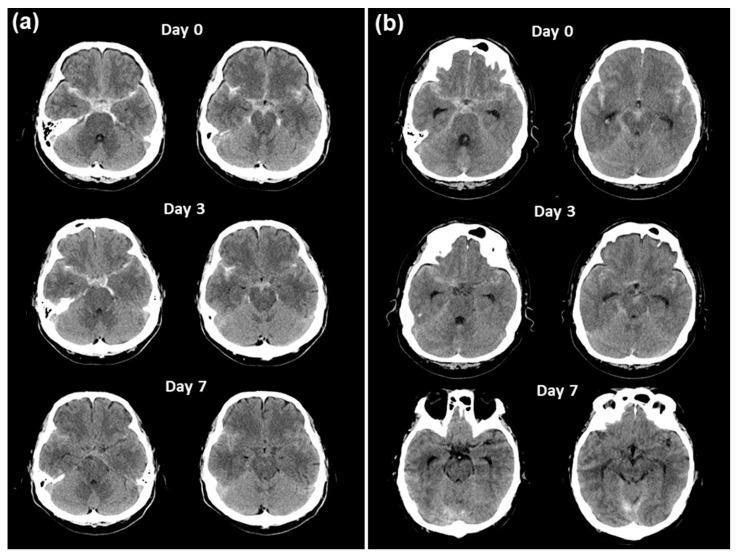

Clazosentan prevents vasospasms after aneurysmal subarachnoid hemorrhage (SAH). However, clinical data on patients with SAH with ruptured vertebral artery dissecting aneurysms (VADAs) are limited. We report the case of a 49-year-old male patient with mild-grade (WFNS grade 1) thick and diffuse (modified Fisher grade 3) SAH who underwent endovascular trapping of a ruptured VADA, resulting in a poor functional outcome with a modified Rankin Scale score of 4 due to severe symptomatic vasospasm refractory to clazosentan, requiring repeated rescue endovascular therapies and chronic communicating hydrocephalus. A retrospective analysis of the clot density in the basal and Sylvian cisterns, assessed by the Hounsfield unit (HU) values of serial CT scans, in this patient showed persistent higher values, distinct from another VADA case that showed a decline in HU values with a good clinical course. These results imply the limited effectiveness of clazosentan in cases of thick and diffuse SAH after a ruptured VADA, even in good-clinical-grade patients treated with less invasive modalities. The HU values may become a simple quantitative marker for predicting symptomatic vasospasms and chronic hydrocephalus.

克拉生坦可预防蛛网膜下腔出血(SAH)后的血管痉挛。然而,关于破裂椎动脉夹层动脉瘤(VADA)的 SAH 患者的临床数据有限。我们报告了一例 49 岁男性患者,其为轻度(WFNS 分级 1)厚且弥漫(改良 Fisher 分级 3)SAH,接受了破裂 VADA 的血管内夹闭术,由于严重的症状性血管痉挛对克拉生坦无反应,需要反复进行血管内救援治疗和慢性交通性脑积水,导致功能预后不良,改良 Rankin 量表评分为 4。对该患者的基底池和外侧裂池的血栓密度进行回顾性分析,通过连续 CT 扫描的亨氏单位(HU)值评估,发现持续存在较高的 HU 值,与另一例 HU 值下降、临床过程良好的 VADA 病例不同。这些结果表明,即使在接受侵袭性较小的治疗方式的良好临床分级患者中,克拉生坦在破裂 VADA 后发生厚且弥漫性 SAH 时的疗效有限。HU 值可能成为预测症状性血管痉挛和慢性脑积水的简单定量标志物。